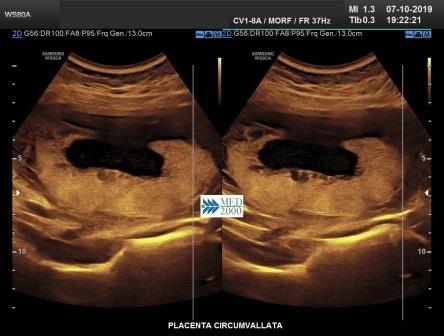

Placenta circumvallata è una patologia che si verifica in circa l' 1% di tutte le gravidanze, dovuta probabilmente ad un impianto più profondo della placenta nella decidua che comporta una discrepanza tra dimensioni del piatto coriale e la base di impianto della placenta. Di conseguenza le membrane corioamniotiche non si inseriscono sul bordo della placenta ma più verso il centro ripiegando su se stesse fino a formare il caratteristico margine circonferenziale arrotolato "tipo cornicione della pizza". Ecograficamente il margine placentare arrotolato che si estende tra i due margini placentari appena al disopra della superficie della placenta appare come una spessa area lineare di echi che attraversa la superficie della placenta assumendo, in sezione trasversa, un "aspetto a mensola". Tale aspetto può simulare una sinechia ma a differenza della placenta circumvallata la sinechia si estende in senso antero-posteriore attraverso la cavità uterina e non ha alcuna relazione con la posizione della placenta, elementi questi che consentono di porre una corretta diagnosi differenziale. La placenta circumvallata può associarsi ad una più alta incidenza di complicanze perinatali come la nascita pretermine, rottura prematura delle membrane (PROM), distacco di placenta.